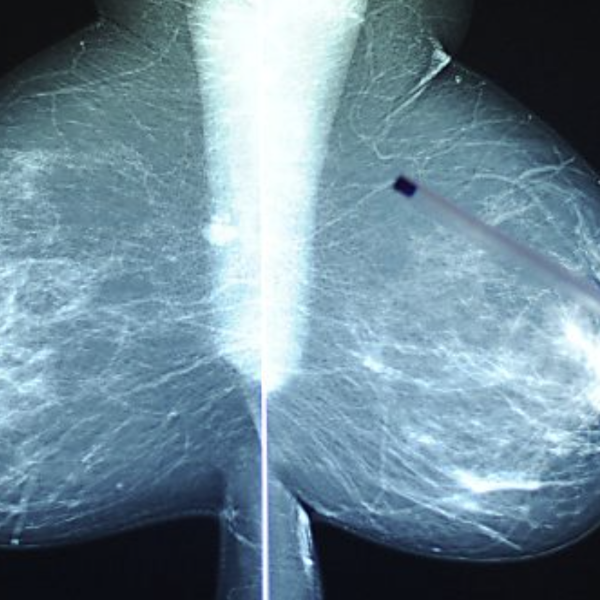

Радиология играет ключевую роль в скрининге и диагностике рака молочной железы. «Мы можем лечить небольшие локальные опухоли максимальным размером от двух до трех сантиметров с помощью минимально инвазивной криотерапии», — пояснил руководитель клиники. Маленькая 1,5-миллиметровая игла вводится в опухоль под местной анестезией и подвергается глубокой заморозке до минус 186 градусов по Цельсию с использованием газообразного аргона или жидкого азота.

Лечение этими «ледяными шариками» убивает опухолевую ткань.